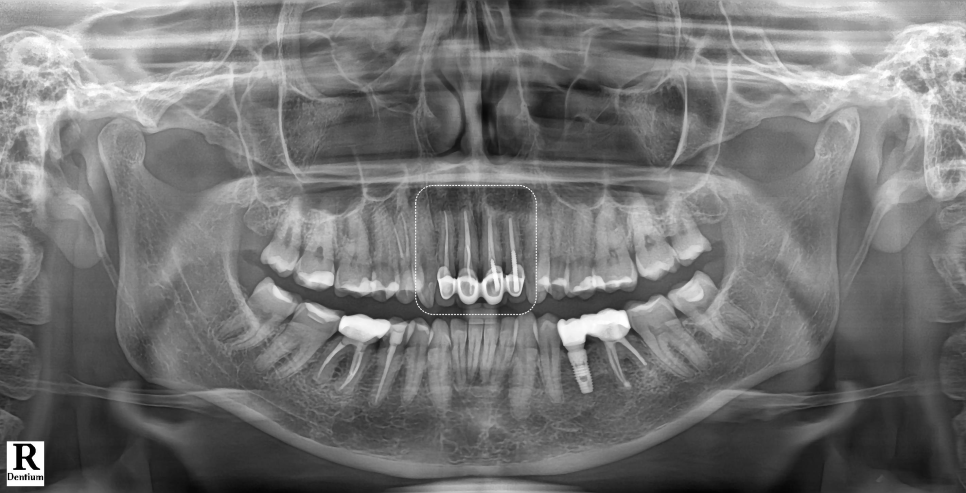

촬영 : 251015

환자분의 앞니는 PFM이라는 재료로 씌워져 있었는데요.

PFM은 Pocelain Fused Metal의 약자로, 메탈 위에 포세린(흰색 도자기)을 얹어서 제작한 보철이에요.

보시는 것처럼, 가장 안에 위치한 메탈이 시간이 지나면서 잇몸이 서서히 퇴축되며 경계부가 드러나 검게 보이게 돼요.

| 2) 브릿지(Bridge)로 제작 |

앞니 4개는 모두 브릿지로 한 덩어리로 연결되어 있었어요.

겉보기엔 단단해 보이지만 실제로는 잇몸이 답답하게 눌리고 치아 사이 위생 관리도 어려운 구조라 가급적이면 하나씩 제작하는 싱글 크라운(Single Crown) 형태가 좋습니다.